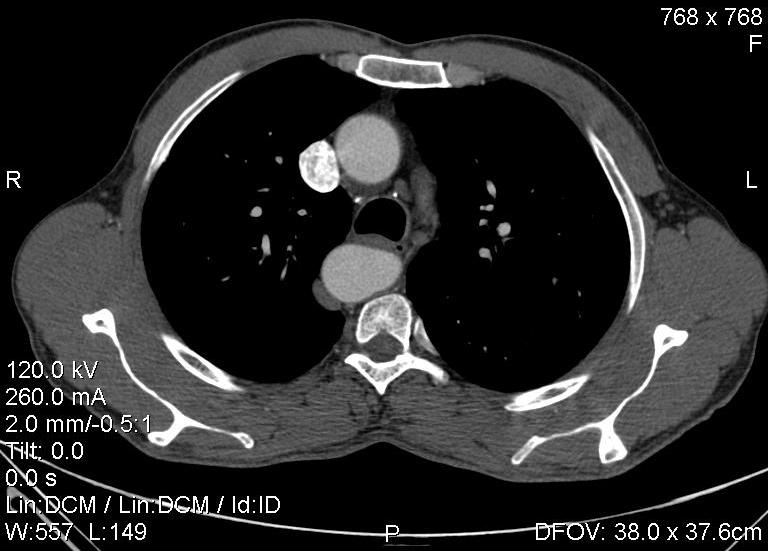

Пациент был направлен на КТ после рентгенографии ОГК, с направительным диагнозом: объёмное образование верхнего средостения.

это аномально расположенная грудная аорта

Конечно, дуга аорты идёт справа от позвоночника (декстра позиция); но есть и ещё одна аномалия той же группы: